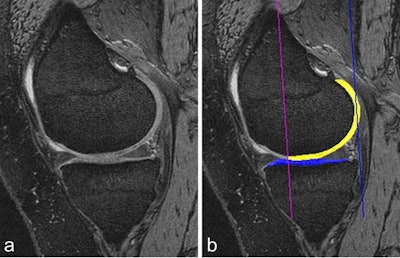

Cartilage quantification based on 3D MRI. A: Sagittal dual-echo at steady-state (DESS) MRI is commonly used for cartilage segmentation. Cartilage appears as a bright signal band between the subchondral bone and the intraarticular cavity. B: The femoral segmentation is color-coded in yellow and the tibial boundaries of cartilage are coded in blue. In addition, the subregional demarcations are shown (purple and blue lines). Image courtesy of Drs. Wolfgang Wirth and Felix Eckstein, Paracelsus Medical University in Salzburg, Austria, and the BJR.Ultrasound's vast potential

For quantitative and qualitative analyses using MRI, Roemer finds 3D morphometry particularly valuable.

"This is based on tissue segmentation and is being widely used for cartilage quantification," he said. "The cartilage tissue is well contrasted between the intra-articular fluid and the subchondral bone. Regions of interests are drawn around the cartilage, and multiple parameters can be extracted from those 3D segmentations, including cartilage volume, cartilage thickness, the amount of the denoted bone area beneath the cartilage, and so on."